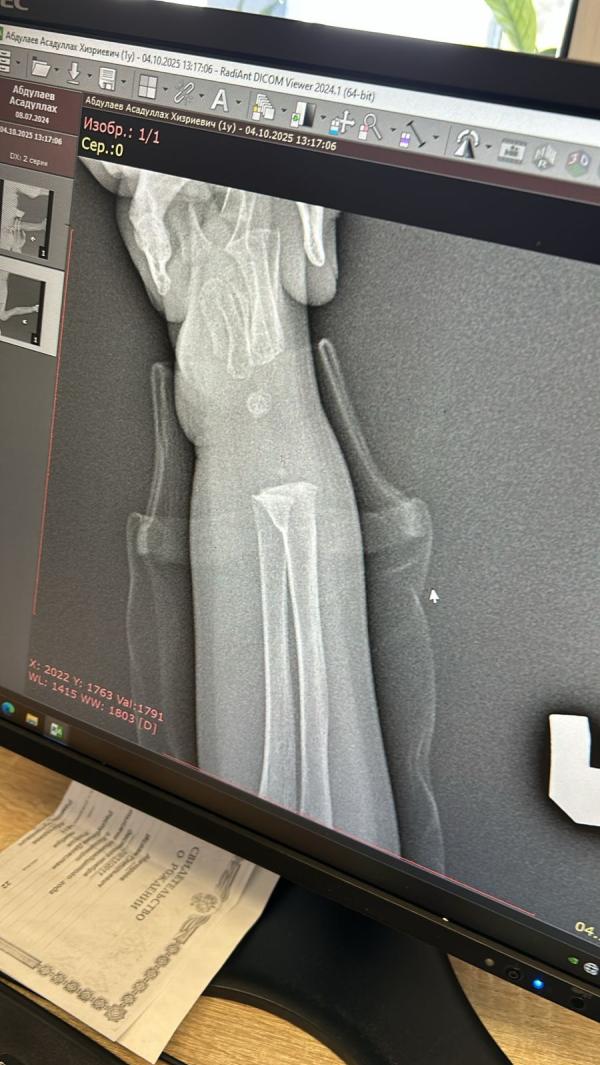

Просто мой малыш ходил два дня с поломанной рукой ….как обычно игрался гулял хорошо себя чувствовал ,а сегодня на третий день я заметила отек на кисти ,думала подвывех бывает же у детей,отправила с мужем в многопроф их чтоб вправили или посмотрели что там ..про осмотре травматолог сразу сказал перелом ,отправили на снимок а там обе кости поломаны ,гипс до плеча …боже мой я в шоке ,наплакалась и сижу жду своего маленького инвалида 😭😭❤️❤️❤️

Судя по этому снимку не серьезный перелом. Ин Ша Аллагь быстро заживет. Тем более у детей

Мне кажется там оторваны будто кости и пробел между ними и будто все ужасно 😭

@nelyu_, нет конечно вы что😄 это же ребенок. У них зоны роста открыты бывают и смещения нет главное. Так что не переживайте 🌸

Врач сказал недельный перелом ,ну недельный точно нет ,3 дня назад он упал и плакал ,в тот день видимо и сломал